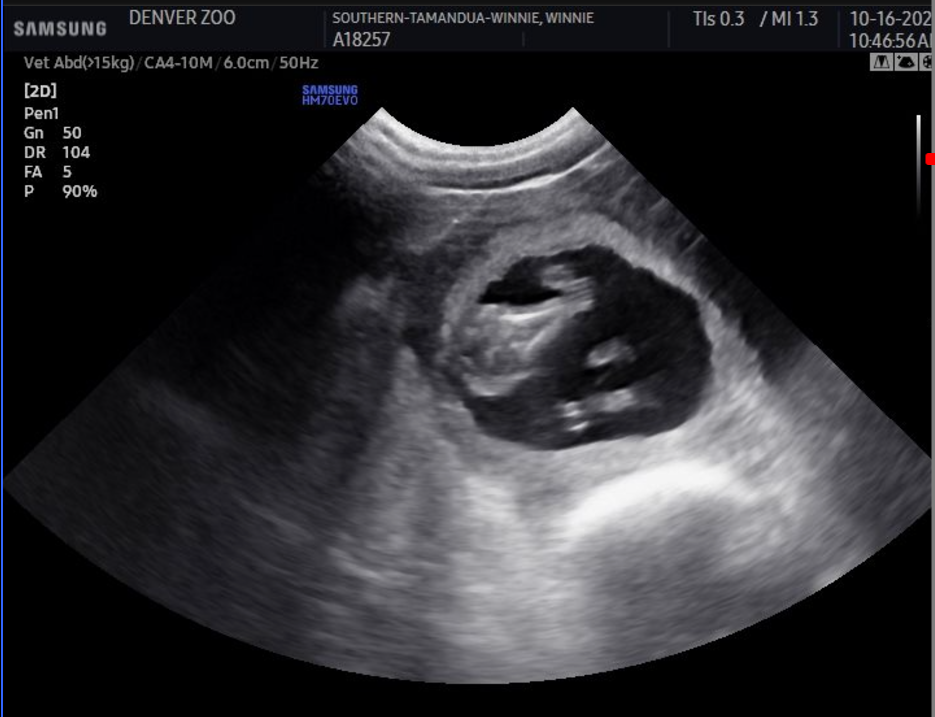

It might seem like a strange pregnancy craving, but Winnie is a tamandua (aka an anteater), after all. Winnie chows down, unconcernedly splattering avocado everywhere as veterinarian Kiran Fong and registered veterinary technician Danielle Coffman perform the ultrasound, capturing images and measurements of Winnie’s baby, which will be the first tamandua born at the Denver Zoo Conservation Alliance in over a decade.

When it was time to announce the pregnancy to the public, Coffman carefully sized and printed out a strip of ultrasound images for Winnie and her partner, Santiago, to hold up for a photo that has amassed over 76,000 likes on the zoo’s Instagram.

While the weekly ultrasounds cannot confirm the sex of the baby, Wanner says that it will be born sometime in January. “Tamandua pregnancies are 130 to 150 days,” she says. “We’re doing a guesstimate window based on measurements Kiran is taking. Those measurements are actually really well-documented in scientific papers for gestational size in tamanduas. Because we were doing practice ultrasounds prior to the baby actually being here, Kiran and I were able to see it when it was just a tiny blip on the radar, so we have a good guess based on when we started seeing something that we can do the math on.” And yes, you can see the tamandua’s prominent snout in the ultrasound.